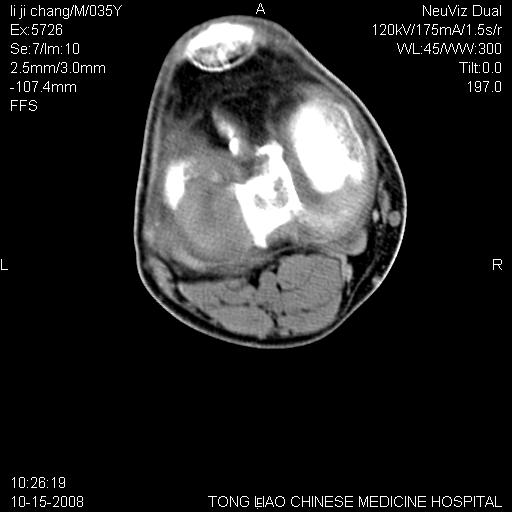

男,35岁,骨科诊断骨性关节炎。继往使用过激素,现股骨头坏死。膝关节病变,请会诊

一元论-----亦考虑为坏死

支持考虑无菌坏死

支持无菌坏死伴退行性骨关节病.

剥脱性骨软骨炎:是一种关节下软骨及软骨下骨缺血性坏死。

支持 无菌性坏死伴退行性骨关节病。